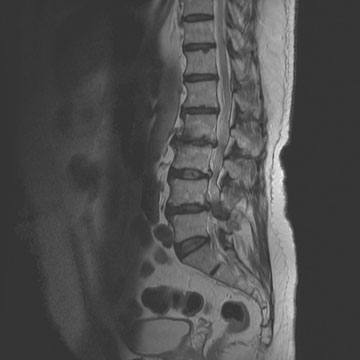

Degenerative